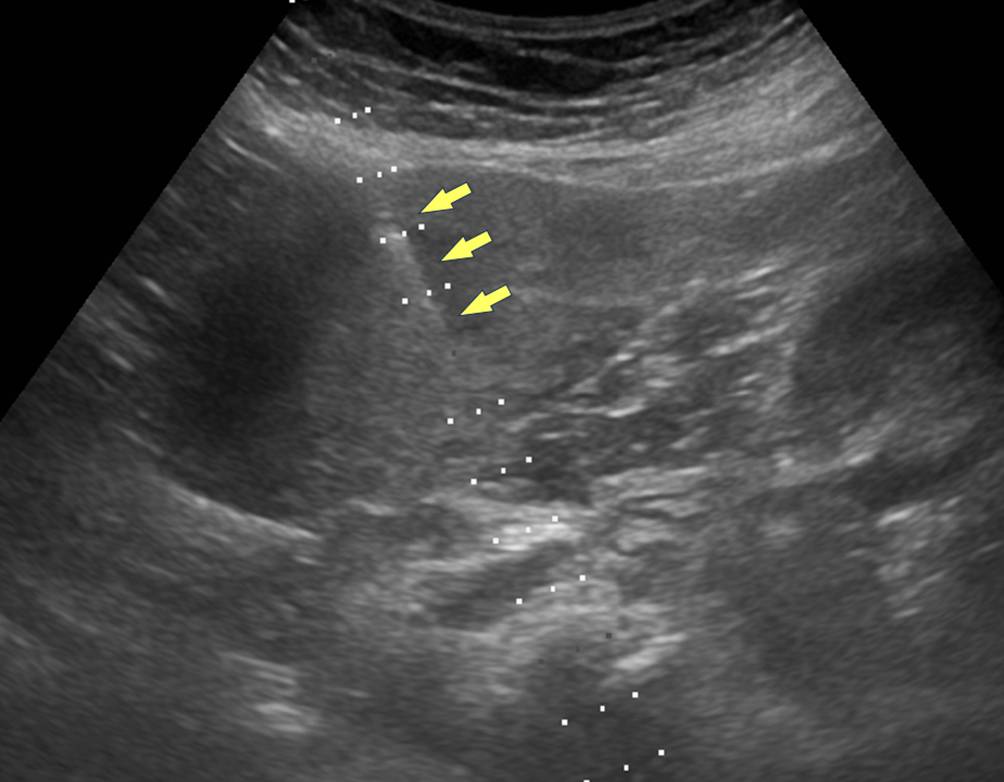

Abb. 2

Der Tumor wurde Ultraschall-gezielt biopsiert (Pfeile)